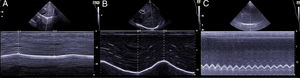

La medición del desplazamiento evalúa la capacidad del diafragma de generar cambios de volumen en la caja torácica. Se realiza un abordaje subcostal, usando una sonda convexa de baja frecuencia a nivel de la línea medio clavicular, buscando el tercio posterior de la cúpula diafragmática en el lado derecho, a través de la ventana hepática. En el lado izquierdo se utiliza la ventana esplénica, pero la cúpula es más difícil de localizar, especialmente si hay interposición de vísceras abdominales6. Una alternativa es el abordaje lateral, colocando la sonda en posición perpendicular en los espacios intercostales inferiores a nivel de la línea medio axilar. Tras la localización de la cúpula en «modo 2D», el modo ecográfico «M anatómico» facilita la identificación de la porción de la cúpula con mayor movilidad, para su medición en un corte sagital. Se mide el desplazamiento en respiración en reposo (volumen corriente), en inspiración y espiración profundas (capacidad vital) o en maniobras de sniff (fig. 1). Puede medirse también su potencia (desplazamiento a lo largo del tiempo, en forma de pendiente de la curva de desplazamiento). En algunas situaciones en las que no se discrimina adecuadamente el diafragma, se puede medir el desplazamiento de vísceras abdominales (vena cava en el lado derecho, o del bazo en el izquierdo), con aceptables resultados. Esto se conoce como «método indirecto»7.

La medición del grosor diafragmático es otro método actualmente empleado, permite determinar la masa muscular diafragmática, y valorar la fracción de engrosamiento, o «thickening fraction» (TF). Para esta medición se utiliza una sonda lineal de alta frecuencia, colocada entre los últimos espacios intercostales. De esta forma se localiza la «zona de aposición», donde el diafragma se inserta en la pared costal. El diafragma se identifica como la franja hipoecogénica limitada por dos líneas hiperrefringentes, que corresponden a la pleura y al peritoneo. El TF es la relación entre el grosor en reposo (capacidad residual funcional) y en máxima inspiración (capacidad vital) (figs. 1 y 2).